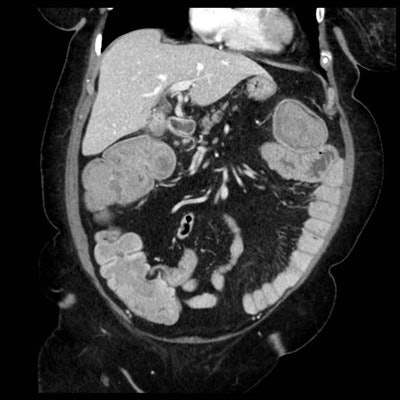

16 enero 2017 -- Historia: Una mujer de 70 años con obstipación y diarrea intermitentes durante una semana. La paciente experimenta dolor a la presión y palpación del cuadrante superior derecho.

A continuación se muestran las imágenes por TC coronales y axiales a través del abdomen superior e inferior.